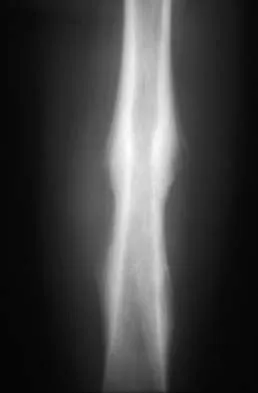

Question 7High Yield

A 15-year-old boy reports leg pain after being tackled during football practice. Radiographs and a CT scan are shown in Figures 46a through 46c. The patient has a pathologic fracture through what underlying lesion?